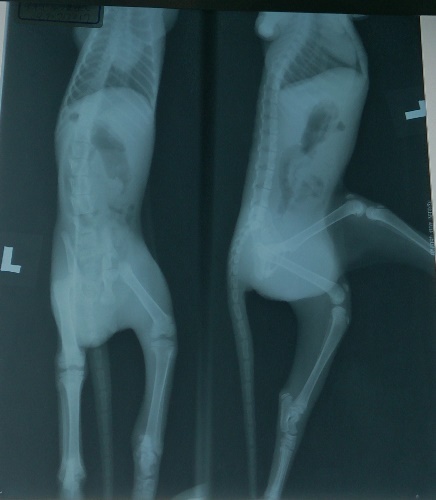

經X光檢查及貓瘟篩檢,目前確診為右側股骨斷裂、

疱診病毒感染、嚴重球蟲感染、蛔蟲、

鼠蹊部出血鼓脹外傷。